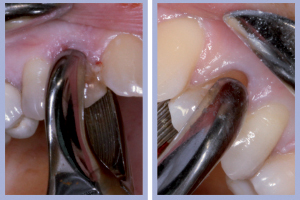

- Figg. 4a, b – Scollamento

- Figg. 5a, b – Estrazione dei canini da latte

- Figg. 6a, b – Estrazione dei canini da latte

- Figg. 7a, b – Toilette chirurgica

- Figg. 8a, b – Mappatura alveolare tramite sonda parodontale